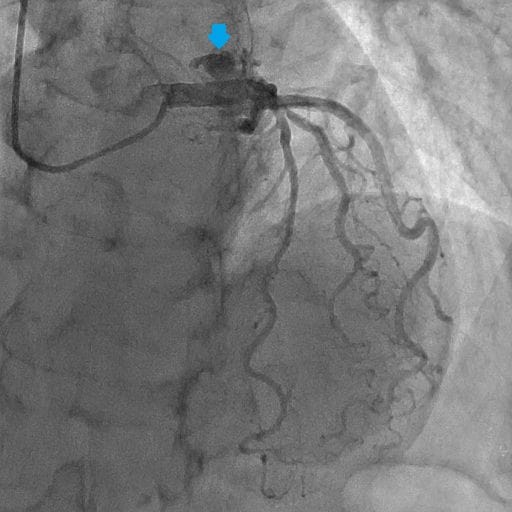

図3.冠動脈造影(左冠動脈)RAO:CAU

左冠動脈造影にて瘤を伴った左冠動脈肺動脈瘻を認める。

図4.冠動脈造影(左冠動脈)LAO:CRA